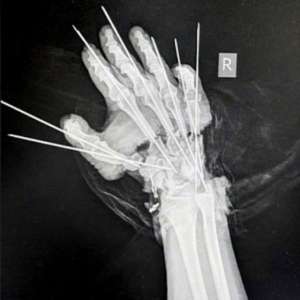

Врачи из Национального медицинского исследовательского центра травматологии и ортопедии имени Р. Р. Вредена совершили настоящий подвиг, спасши руку молодой девушке, которую во время работы на станке буквально отрезало.

28-летняя пациентка потеряла кисть, но благодаря усилиям врачей Артёма Афанасьева и Александра Чижова, которые провели семь часов за операционным столом, её рука была собрана буквально по кусочкам. Под микроскопом они соединили вены, артерии, сухожилия и нервы, вернув девушке способность двигаться и жить полноценной жизнью.

Конечно, после такого серьёзного хирургического вмешательства не избежать некоторых последствий, но в целом пациентка будет жить полноценной жизнью, имея две руки.

Мы желаем ей скорейшего выздоровления и выражаем огромную благодарность врачам Национального медицинского исследовательского центра травматологии и ортопедии имени Р. Р. Вредена за их профессионализм и преданность делу.